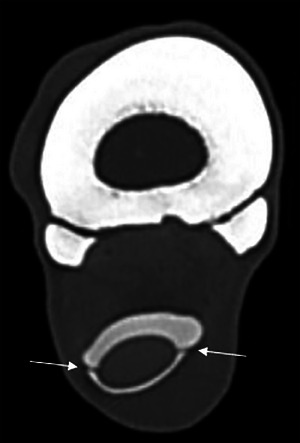

Exploratory tenoscopy is considered the gold standard technique to identify intrathecal pathology of the equine carpal flexor tendon sheath (CFTS). Preoperative diagnosis allows for more precise prognostication and surgical planning, potentially associated with improved surgical outcomes. This prospective, descriptive, anatomical study aimed to describe the anatomy of the equine CFTS using noncontrast and contrast CT in clinically normal cadaver limbs. Ten pairs of equine forelimbs free of gross external abnormalities were examined from mid-antebrachium to distal metacarpus. Specimens initially underwent noncontrast CT examination using 135 kVp, dynamic mAs, and 1 mm slice thickness. Contrast media (iohexol) diluted in saline (total 60 mL, final concentration 75 mg/mL) was injected into the CFTS from a lateral approach before the CT examination was repeated. Tenoscopy was then performed using the conventional lateral approach. Dissection was used to compare the gross, tenoscopic, and imaging findings. The combined noncontrast CT and contrast CT examinations provided excellent anatomical detail of intrathecal and extrathecal structures. Detailed anatomy of the previously undescribed proximal mesotenon and manica of the common mesotenon were also identified. The distal termination of the CFTS was beyond the mid-metacarpus in most specimens, which is significantly more distal than previously reported. This is an important consideration when administering local anesthesia in orthopedic examinations to prevent potential iatrogenic CFTS penetration, which may induce sepsis if the aseptic technique is not followed. Noncontrast and contrast CT can be used to accurately identify CFTS anatomy. Documentation of new intrathecal structures provides a greater understanding of CFTS anatomy.